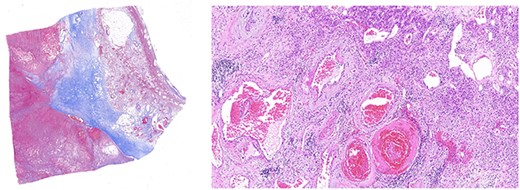

Left panel: low magnification (20×) of Masson’s trichrome stain highlighting fibrosis, fibrin and haemangioma in the adrenal cortex. Right panel: medium magnification (200×) of haematoxin- and eosin-stained section demonstrating variably dilated vascular changes filled with blood with variable hyalinization and fibrin in the wall.

Histologically, adrenal haemangiomas can be subtyped into cavernous, capillary, venous and mixed [11]. Cavernous haemangiomas have well-defined margins and are usually confined to the adrenal cortex. They exhibit numerous dilated vascular channels lined by bland endothelium, and with repeated haemorrhage can show complex necrotic, calcified, fibrotic and thrombotic changes, features compatible with reorganization (‘pseudocyst’) [12]. In our case, these features were well evident (Fig. 5).